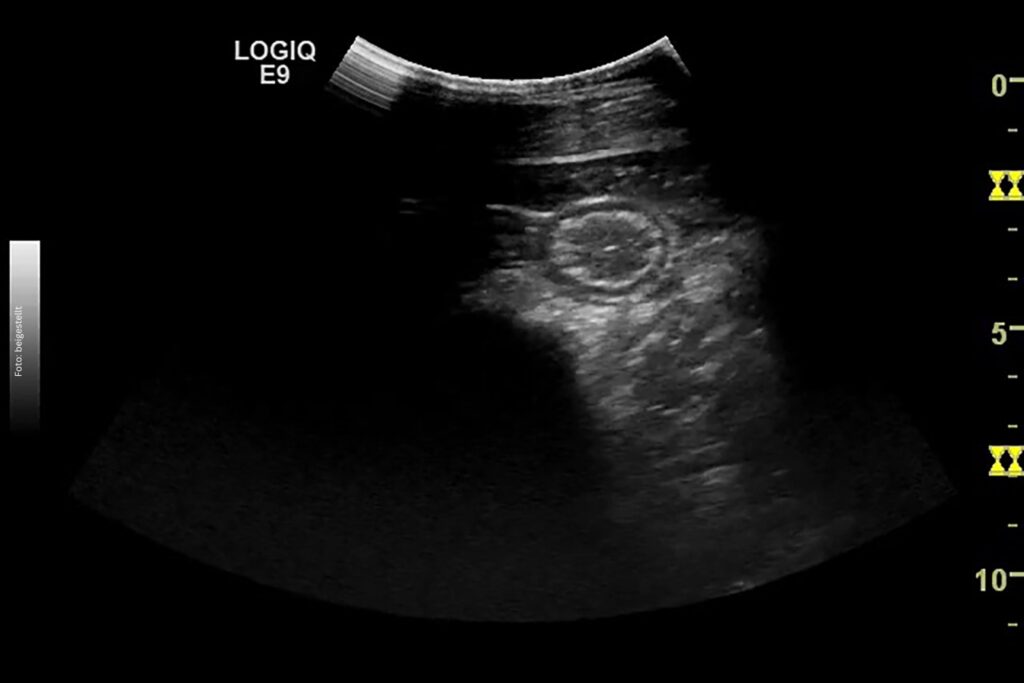

Der nächste Schritt ist ein Abdomenultraschall: Hier ist bei einer IBD eine Verdickung der Darmschleimhaut zu erwarten. Die Dünndarmschleimhaut sollte ja drei bis vier Millimeter dick sein. Ein Wert über 5,7 mm zeigt deutlich an, dass etwas nicht in Ordnung ist. Außerdem achte ich darauf, ob die Veränderungen gleichmäßig verteilt sind oder nur einzelne Darmschlingen stark verdickt sind. Ein weiterer diagnostischer Schritt ist die Abdominozentese: Hier werden das Totalprotein, die Gesamtzellzahl sowie das Laktat gemessen. Dies ist auch wichtig, um ein Lymphom, eine weitere Differentialdiagnose, ausschließen zu können, wobei hier das Bauchhöhlenpunktat auch unverändert sein kann. Bei den meisten Pferden mit IBD ist das Totalprotein nicht verändert.